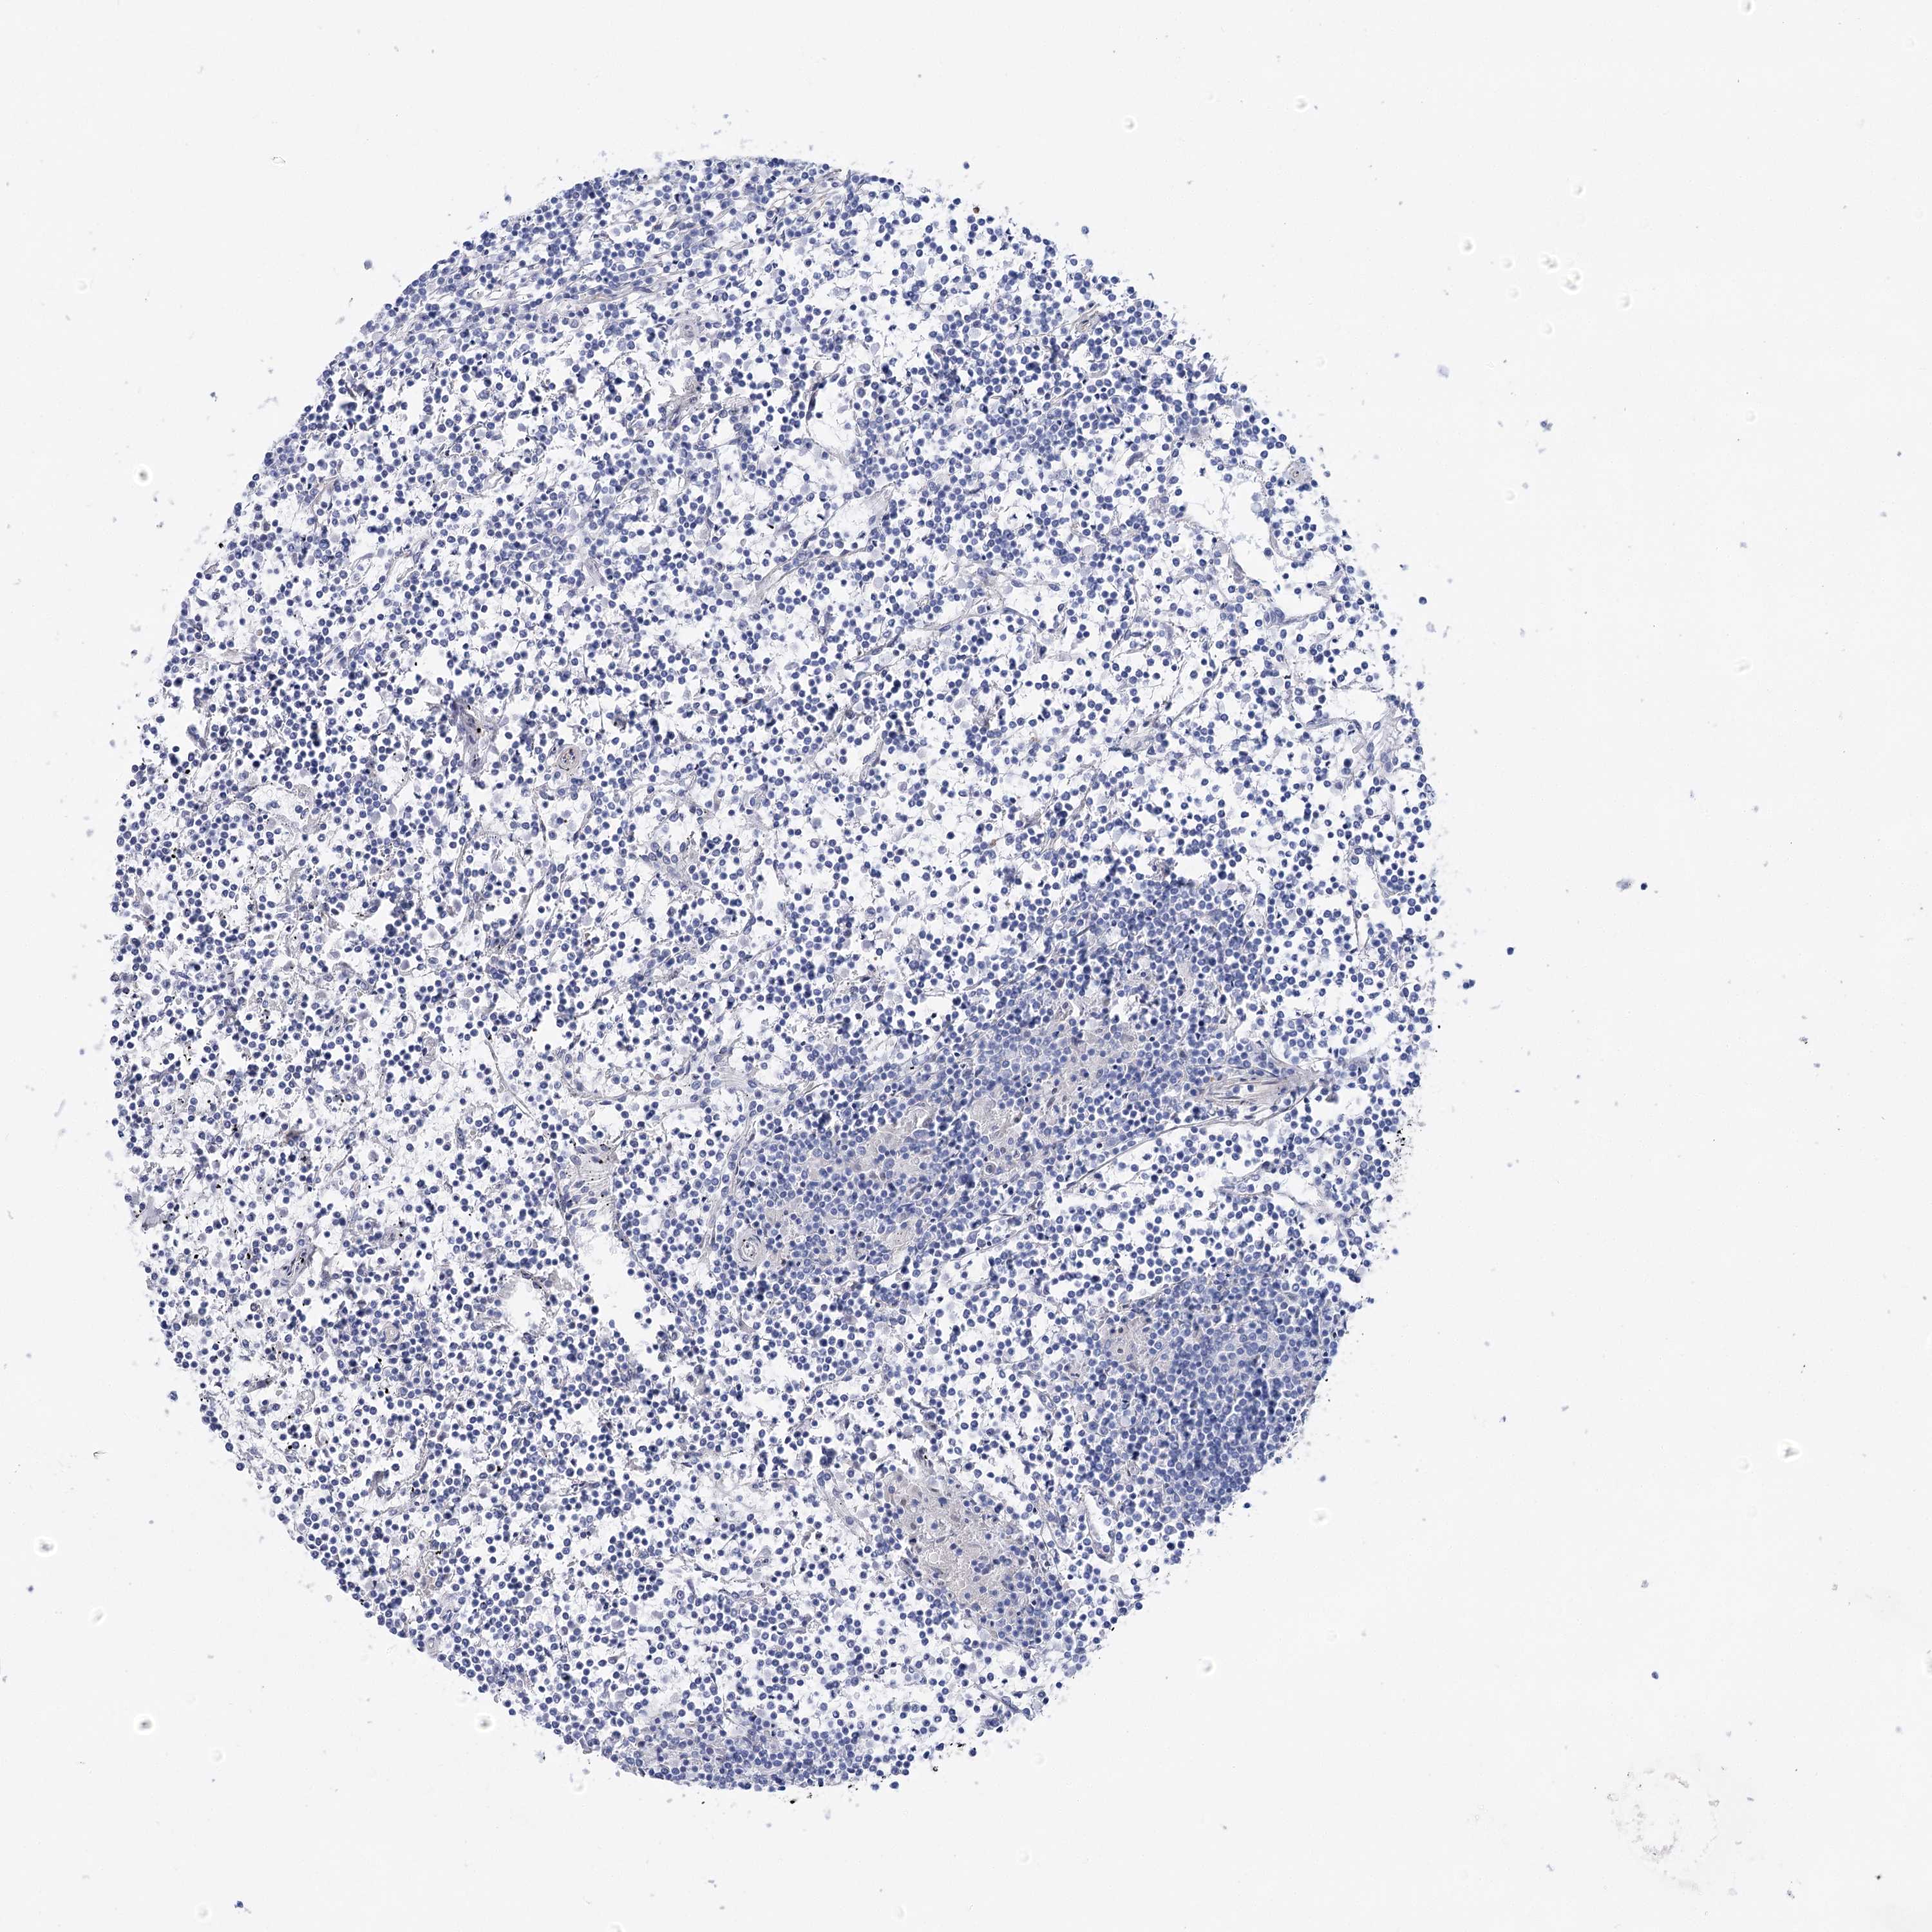

LYMPHOMA - Protein expressioni

A mouse-over function shows sample information and annotation data. Click on an image to view it in a full screen mode. Samples can be filtered based on level of antibody staining by selecting one or several of the following categories: high, medium, low and not detected. The assay and annotation is described here.

Each image is clickable and will lead to virtual microscopy that enables deeper exploration of all samples and also displays staining intensity scores, fraction scores and subcellular localization as well as patient and tissue information for each sample.

Antibody HPA036201

Hodgkin's disease, NOS

Malignant lymphoma, non-Hodgkin's type, High grade

Malignant lymphoma, non-Hodgkin's type, Low grade